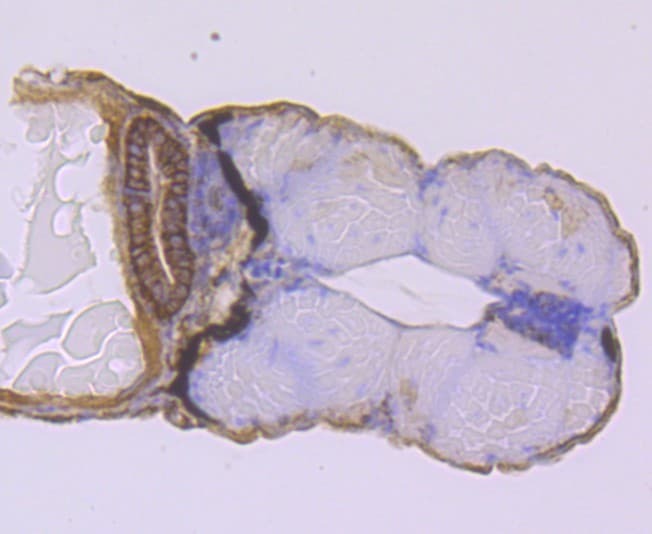

- Experimental details

- Immunohistochemistry analysis of NCAM/CD56 in paraffin-embedded zebrafish tissue. The section was pre-treated using heat mediated antigen retrieval with Tris-EDTA buffer (pH 8.0-8.4) for 20 minutes. The tissues were blocked in 5% BSA for 30 minutes at room temperature, washed with ddH2O and PBS, and then probed with NCAM/CD56 Monoclonal antibody (Product # MA5-45014) using a dilution of 1:50 for 30 minutes at room temperature. The detection was performed using an HRP conjugated compact polymer system. DAB was used as the chromogen. Tissues were counterstained with hematoxylin and mounted with DPX.